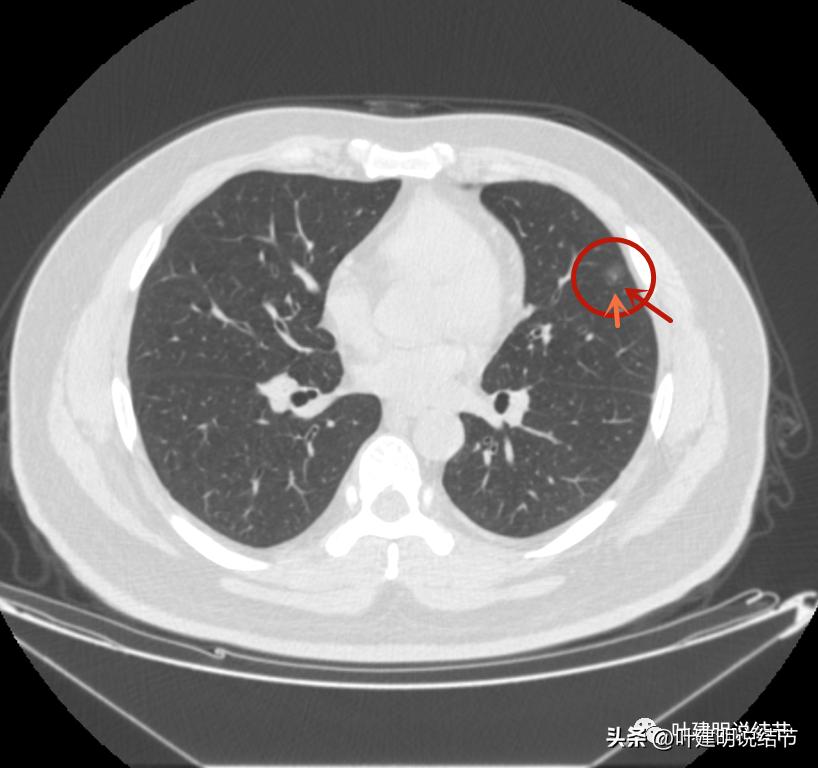

左上病灶2:混合磨玻璃结节,密度偏高,边缘稍糊,但轮廓相对清,有微血管分支进入,考虑微浸润性腺癌或浸润性腺癌可能大;

病灶2出现,还只有一点点磨玻璃影,血管走行有点异样

密度略显高,有微血管进入(桔色箭头),边缘略模糊,但轮廓还是较清

中间有实性成分出现(粉色箭头),微血管进入明显(桔色箭头),边上有磨玻璃成分(绿色箭头),整体轮廓清

病灶密度不均

密度不均显杂乱

表面略不平

整体瘤肺边界与轮廓较清